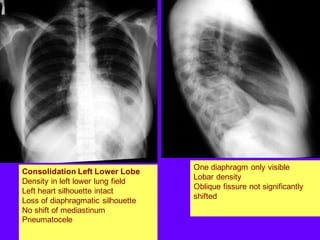

Consolidation Left Lower Lobe

Density in left lower lung field

Left heart silhouette intact

Loss of diaphragmatic silhouette

No shift of mediastinum

Pneumatocele

One diaphragm only visible

Lobar density

Oblique fissure not significantly

shifted